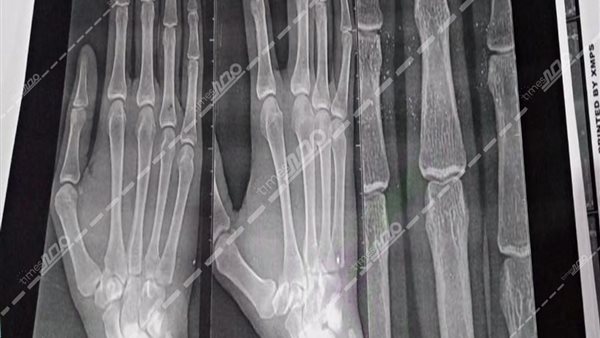

حصل "مصر تايمز" على صور الأشعة التي أجراها طبيب جراحة على يديه، بعد التعدي عليه من قبل أسرة مريض أثناء عمله داخل مستشفى قنا العام، والتي وضحت كسر في أحد صوابعه.

وعلى الفور انتقلت قوة أمنية برئاسة المقدم محمود حمد الله، رئيس مباحث قسم قنا، إلى المستشفى وتبين إصابة طبيب جراحة، بكسر في أحد صوابعه وكدمات بالوجه إثر التعدي عليه من أسرة مريض.